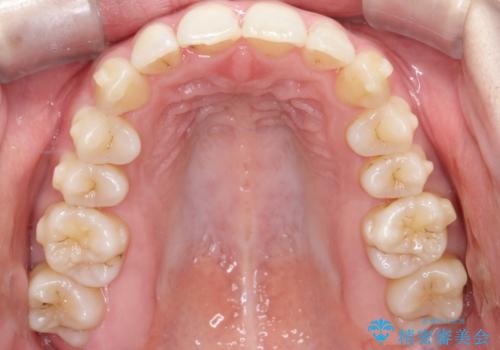

【インビザライン】 前歯の反対咬合を治したい

左下5番は先天性欠損のため乳歯は抜歯しインプラントにて欠損補綴しています。